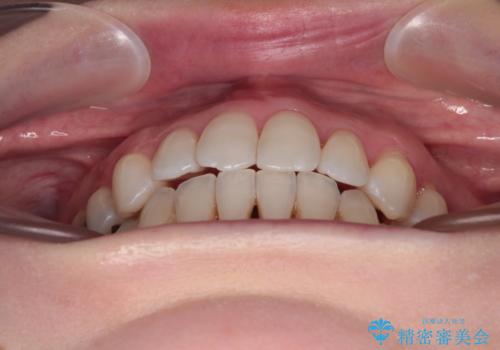

イレギュラーな大臼歯抜歯矯正であったため、治療期間の長期化が想定されましたが、何とか3年ちょうどで終えることができました。

今後は目立っている銀歯を中心にセラミッククラウンなどへ交換していく予定です。